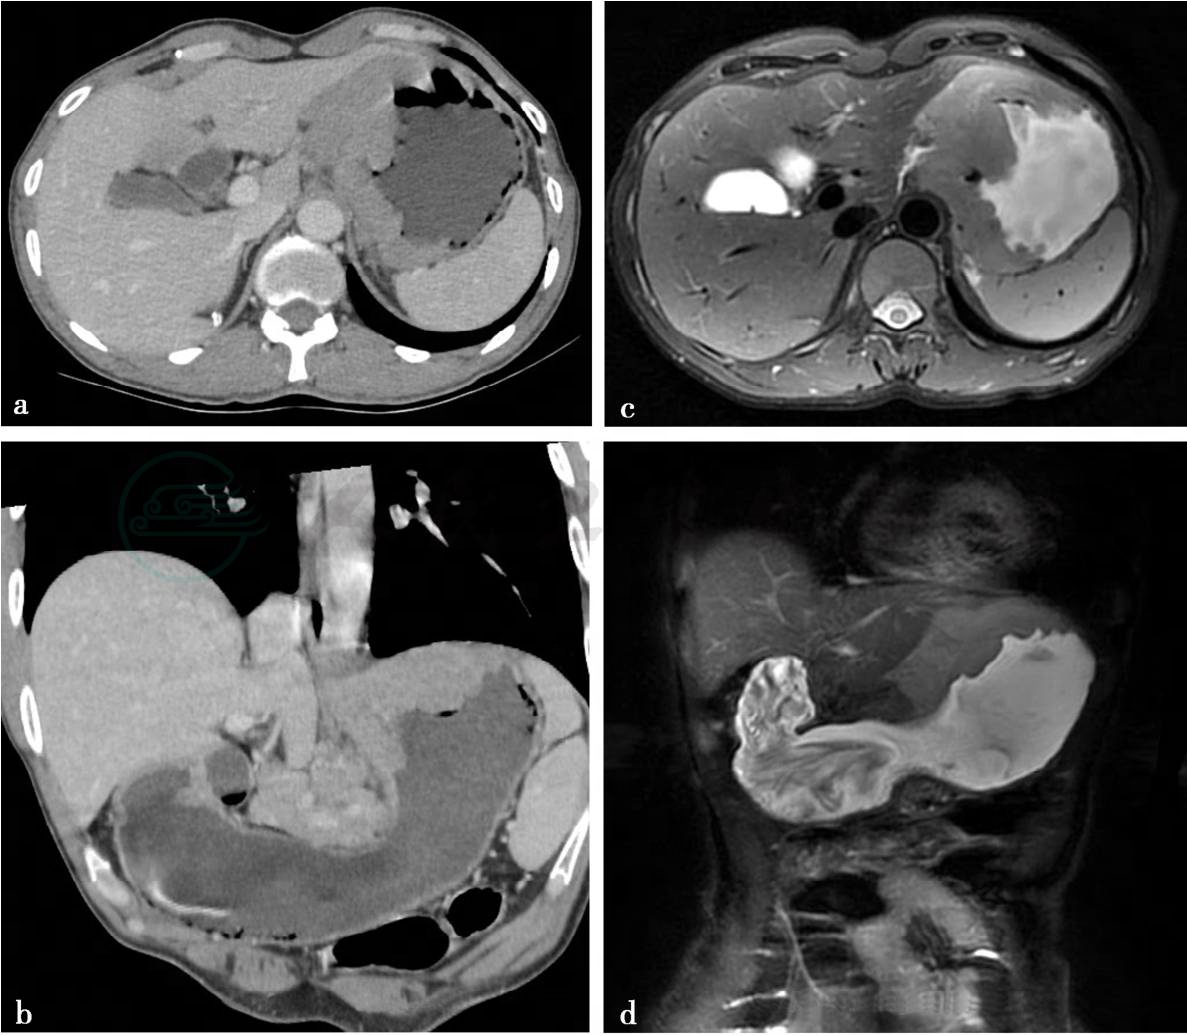

CT增强扫描重建图及MRI扫描(贲门胃底淋巴瘤)。

图2 图2a,CT增强静脉期。图2b,MPR重建图。图2c,轴位T2WI。图2d,冠位T2WI。贲门胃底可见广泛增厚,CT上轻度强化,MRI上呈稍长T2信号